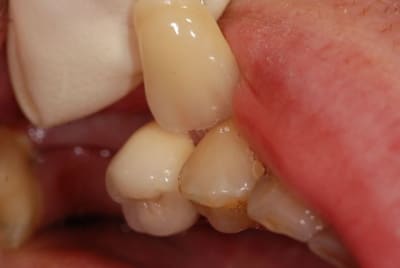

Regardez ce que je viens de recevoir de mon prothésiste habituel.

Vous conviendrez que le résultat n'est pas terrible, mais est assez représentatif de ce que je reçois.

A chaque fois, je met en cause mes piètres talents de prise de teinte, mais vous constaterez sur la deuxième photo que j'étais quand même plus proche que lui.

Alors est-ce qu'on arrive aux limites des CCM ?

Ou faut-il que je change de prothésiste (suggestions sur Paris/RP en MP, merci) ?

'tain là on est dans le B1 en plus elle est hyper opaque

"" Alors est-ce qu'on arrive aux limites des CCM ? ""

des CCM non, mais celles de ton prothé ça a l'air ^^

Le teintier que je présente est un A3,5.

Merci de me confirmer que je ne suis pas un chieur...

Au niveau opacité c'est à peu près ce que j'ai régulièrement.

Je me disais, pour du moyen-haut de gamme, tu ne peux pas avoir la lune. Vos 45 euros sont très éloignés du prix payé.

c'est une ccm monocouche avec un peu de maquillage au collet ,maqquillage qui finira par s'en aller..

trop globuleuse et epaisse (maisquelle epaaisseur lui as tu laissé?)

et pas très bien sculptée(mais qu'y a t'il en face?)